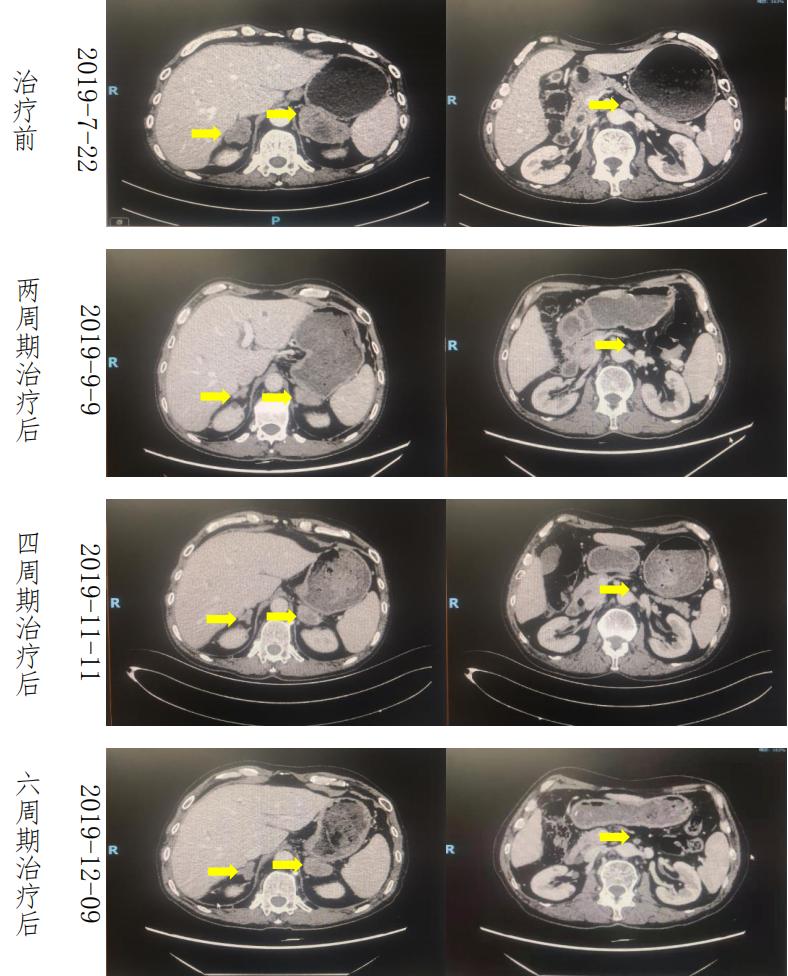

疗效评估 :一线 Xelox 方案化疗 2 周期后肾上腺肿瘤明显退缩,腹膜后淋巴结明显缩小,疗效评估(PR),一线方案治疗 6 周期后疗效评价(SD),肿瘤稍增大;一线治疗 4 周期后血 CA199 出现回升,6 周期治疗后 CA199 明显升高。

肿瘤标记物:标记物在化疗前 2 周期明显降低,4 周期之后 CA199 回升明显。

患者经一线 Xelox 方案化疗 6 周期后,肿瘤体积对比基线缩小,但 6 周期评 估时,肿瘤较 4 周期评估时肾上腺肿块稍增大、标记物 CA199 升高且出现奥沙利 铂相关神经毒性;考虑到患者后期对 Xelox 方案耐受差,且获益有限,我们决定 更改后续治疗方案。鉴于患者肿瘤突变负荷相对较高,且组织中肿瘤细胞 70%表 达 PD-L1。于 2019 年 12 月 10 日至 2020 年 05 月 19 日改行二线化疗联合免疫(伊立替康+卡瑞丽珠单抗)治疗 6 周期。2020 年 06 月 12 日至 2021 年 02 月 26 日 予以 7 周期卡瑞丽珠单抗维持治疗。不良反应:治疗 4 周期后患者腹部、颜面部出现卡瑞利珠单抗相关反应性毛细血管增生。